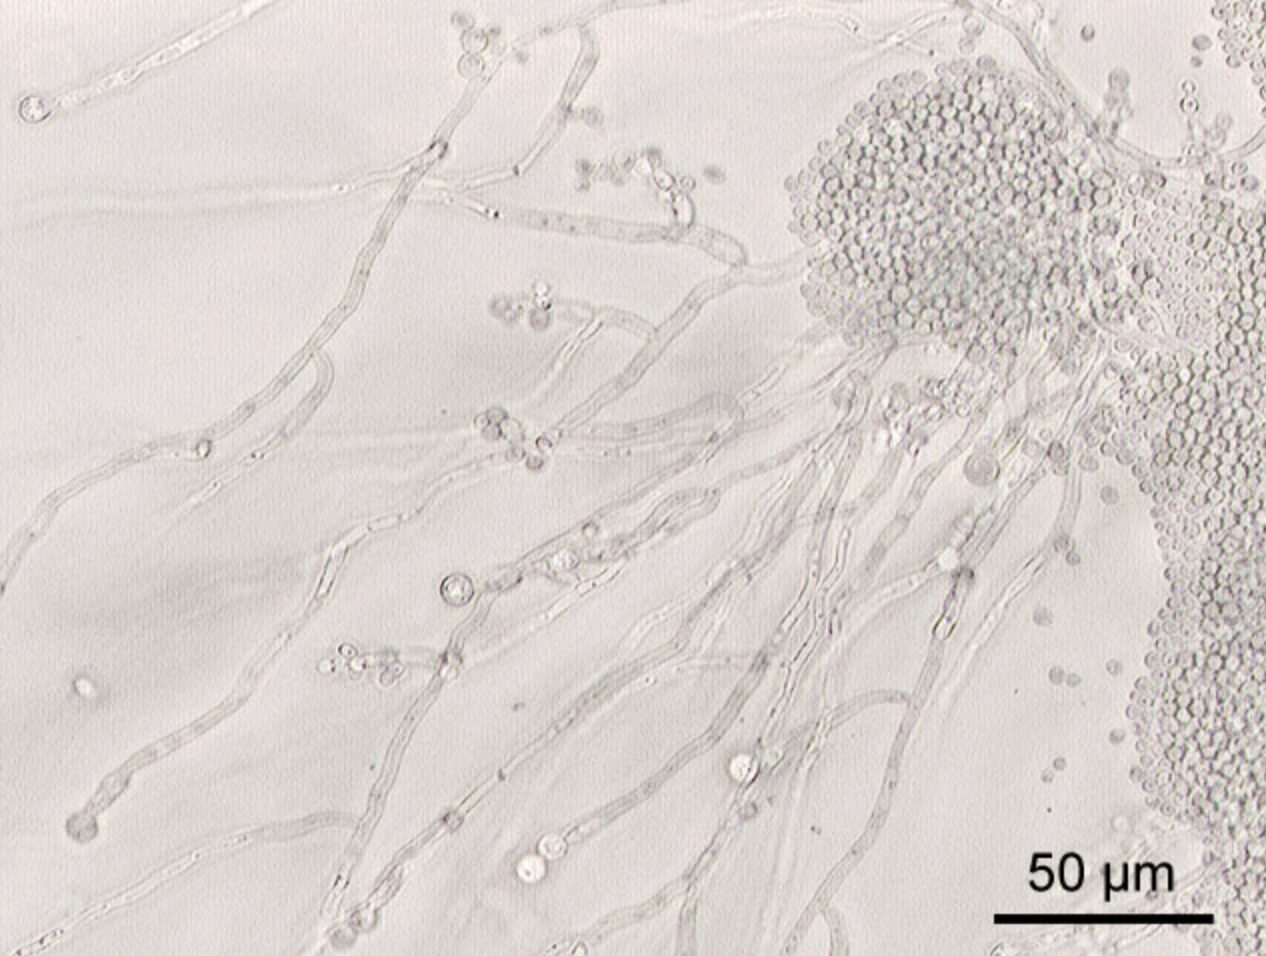

カンジダの検査では、膣分泌物や尿などを採取し、顕微鏡や培養検査によって菌の有無を確認します。もっとも一般的なのは「鏡検法」と呼ばれる方法で、採取した分泌物を顕微鏡で観察し、カンジダ菌の形状や特徴的な分泌物を直接確認します。短時間で結果がわかるため、症状がある場合にすぐ診断できるのが特徴です。